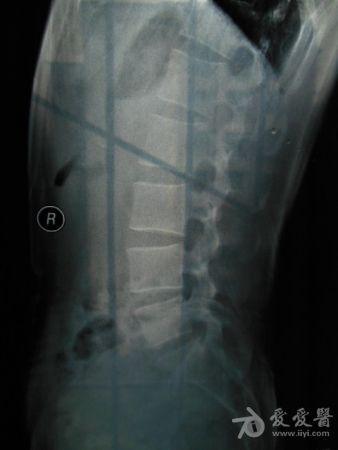

请老师看看这个腰椎和盆骨的平片有无问题

摔了一跤右臀着地,同时闪到腰,查出有椎间盘突出,目前是右臀麻木,整个右腿酸胀沉重。肌力正常走路正常,坐不到5分钟右腿就酸胀难忍。明显觉得左右**感觉不一样,右边软得多,

自觉下腰和盆骨感觉别捏,有歪斜感,扭腰时觉得舒服。腰4右侧一下有异物感。今天照了个腰椎正侧位和盆骨的正位平片,医生说没什么问题,拿来请各位老师看看腰椎和盆骨有没有错位,旋转,不等高等情况,再次感谢。

照该片看应该是骨盆旋移

这种症状拍平片没有什么意义,选择MRI或者CT吧

看片子没发现什么大的问题,没有骨折,没有增生。腰椎间盘突出做核磁共振最清楚。